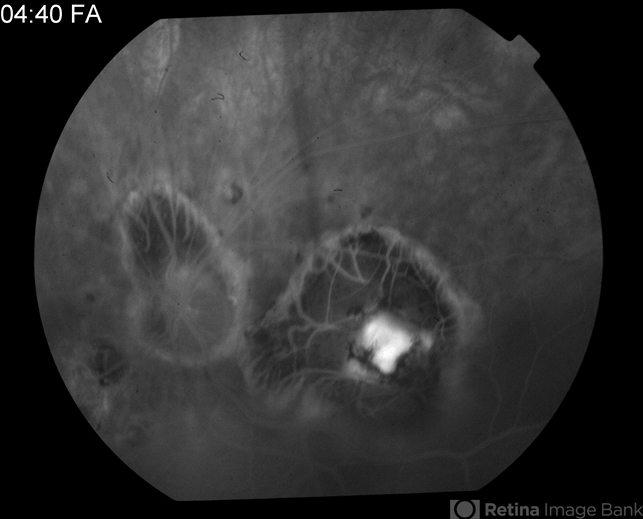

- tuberculosis, macular scar

- Tom Steele, CRA Midwest Eye Institute Indianapolis, Indiana

- Fundus camera

- 4:40 minute FA of 81-year-old male - old tuberculosis scar.